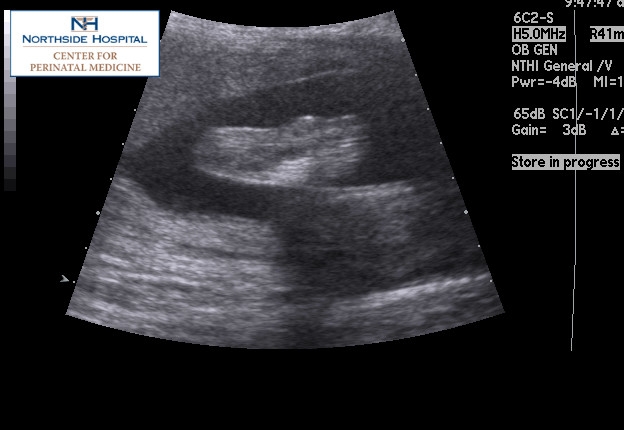

DH and I just got in from my perinatal doc. Michael is weighing in at 1 lb 14 ozs (I'm kinda freaking out, as that seems big), and looks good. Here's a pic of him pushing his hands and feet against me, and another of just his feet.

I also had another U/S cos they couldn't get a good measurement of his spine the last time, so that was first. I had my mom with since DH couldn't make it, and I know she enjoyed seeing her grandbaby on the screen. However, he wasn't cooperating and they couldn't get another measurement. So, I get to have another U/S done 9/20. This is the same day as my already scheduled Glucose Test and checkup... so I am basically spending my day at the hospital (11:45 U/S, 1:10 Glucose, 1:30 appt).

My OB said that there wasn't any big concerns with it, just that they couldn't get what they wanted. I guess I don't mind seeing him again, but am not looking forward to paying it 3X.